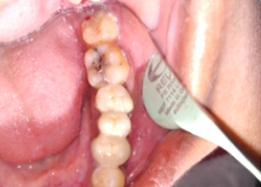

PRE OP Clinical Photograph Measuring Probing Depth

Hemisectomy